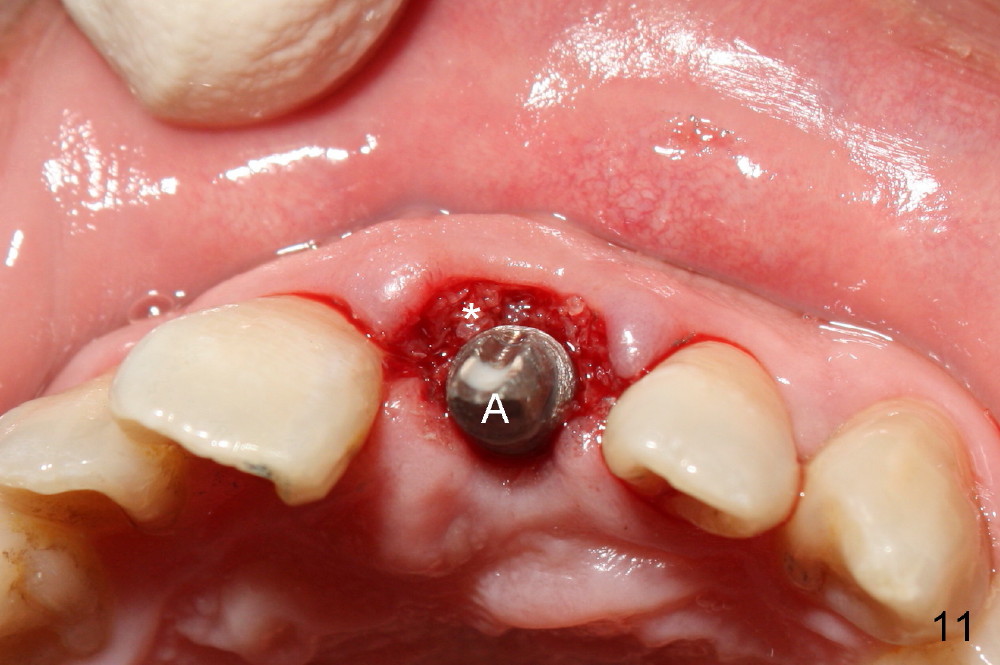

Bone expansion allows the implant (Fig.9 I) to have primary stability (insertion torque between 50 and 60 Ncm), since the cortex of the incisive canal is apparently intact. Allograft is placed in the labial gap (Fig.10, 11 *) following installation of the abutment (A). Finally an immediate provisional (Fig.10,12 P) is cemented. Fig.13,14 are taken 8 days postop. The patient returns 3 months postop (Fig.15,16). Osteointegration appears to have occurred (Fig.15 arrowheads) and is more obvious 9 months postop (Fig.17).